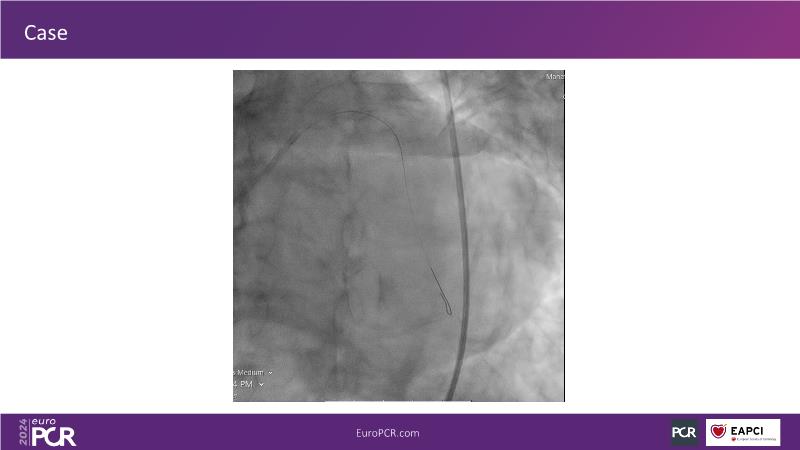

Tune into this 2024 session for insights into the latest ESC guidelines, strategies to prevent and treat no reflow, and an examination of trials like TASTE, TAPAS, and TOTAL on coronary thrombus management. Explore also the outcomes of the CHEETAH study, pondering a potential paradigm shift, and delve into a case study on thrombus removal in a patient with high thrombus burden.